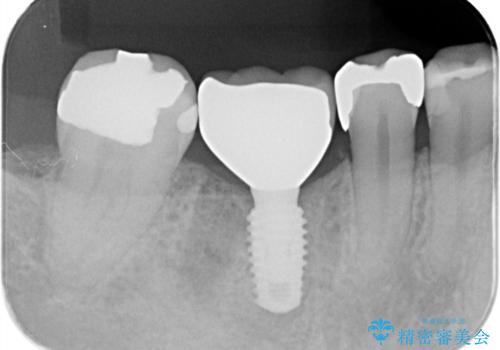

骨の量は十分あったため、比較的短期間で治療は終了しました。

安定した咬み合わせとなり、痛みもなく安心して噛めるようになりました。